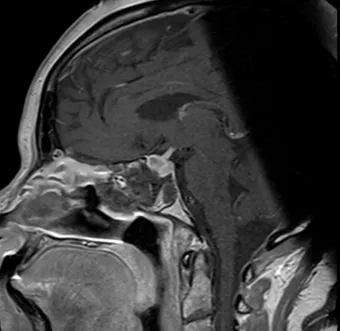

Pre- and Post-Op Pituitary Macroadenoma

Pre Op Pituitary Tumor Image 1

Pre-Op Image of Pituitary Tumor